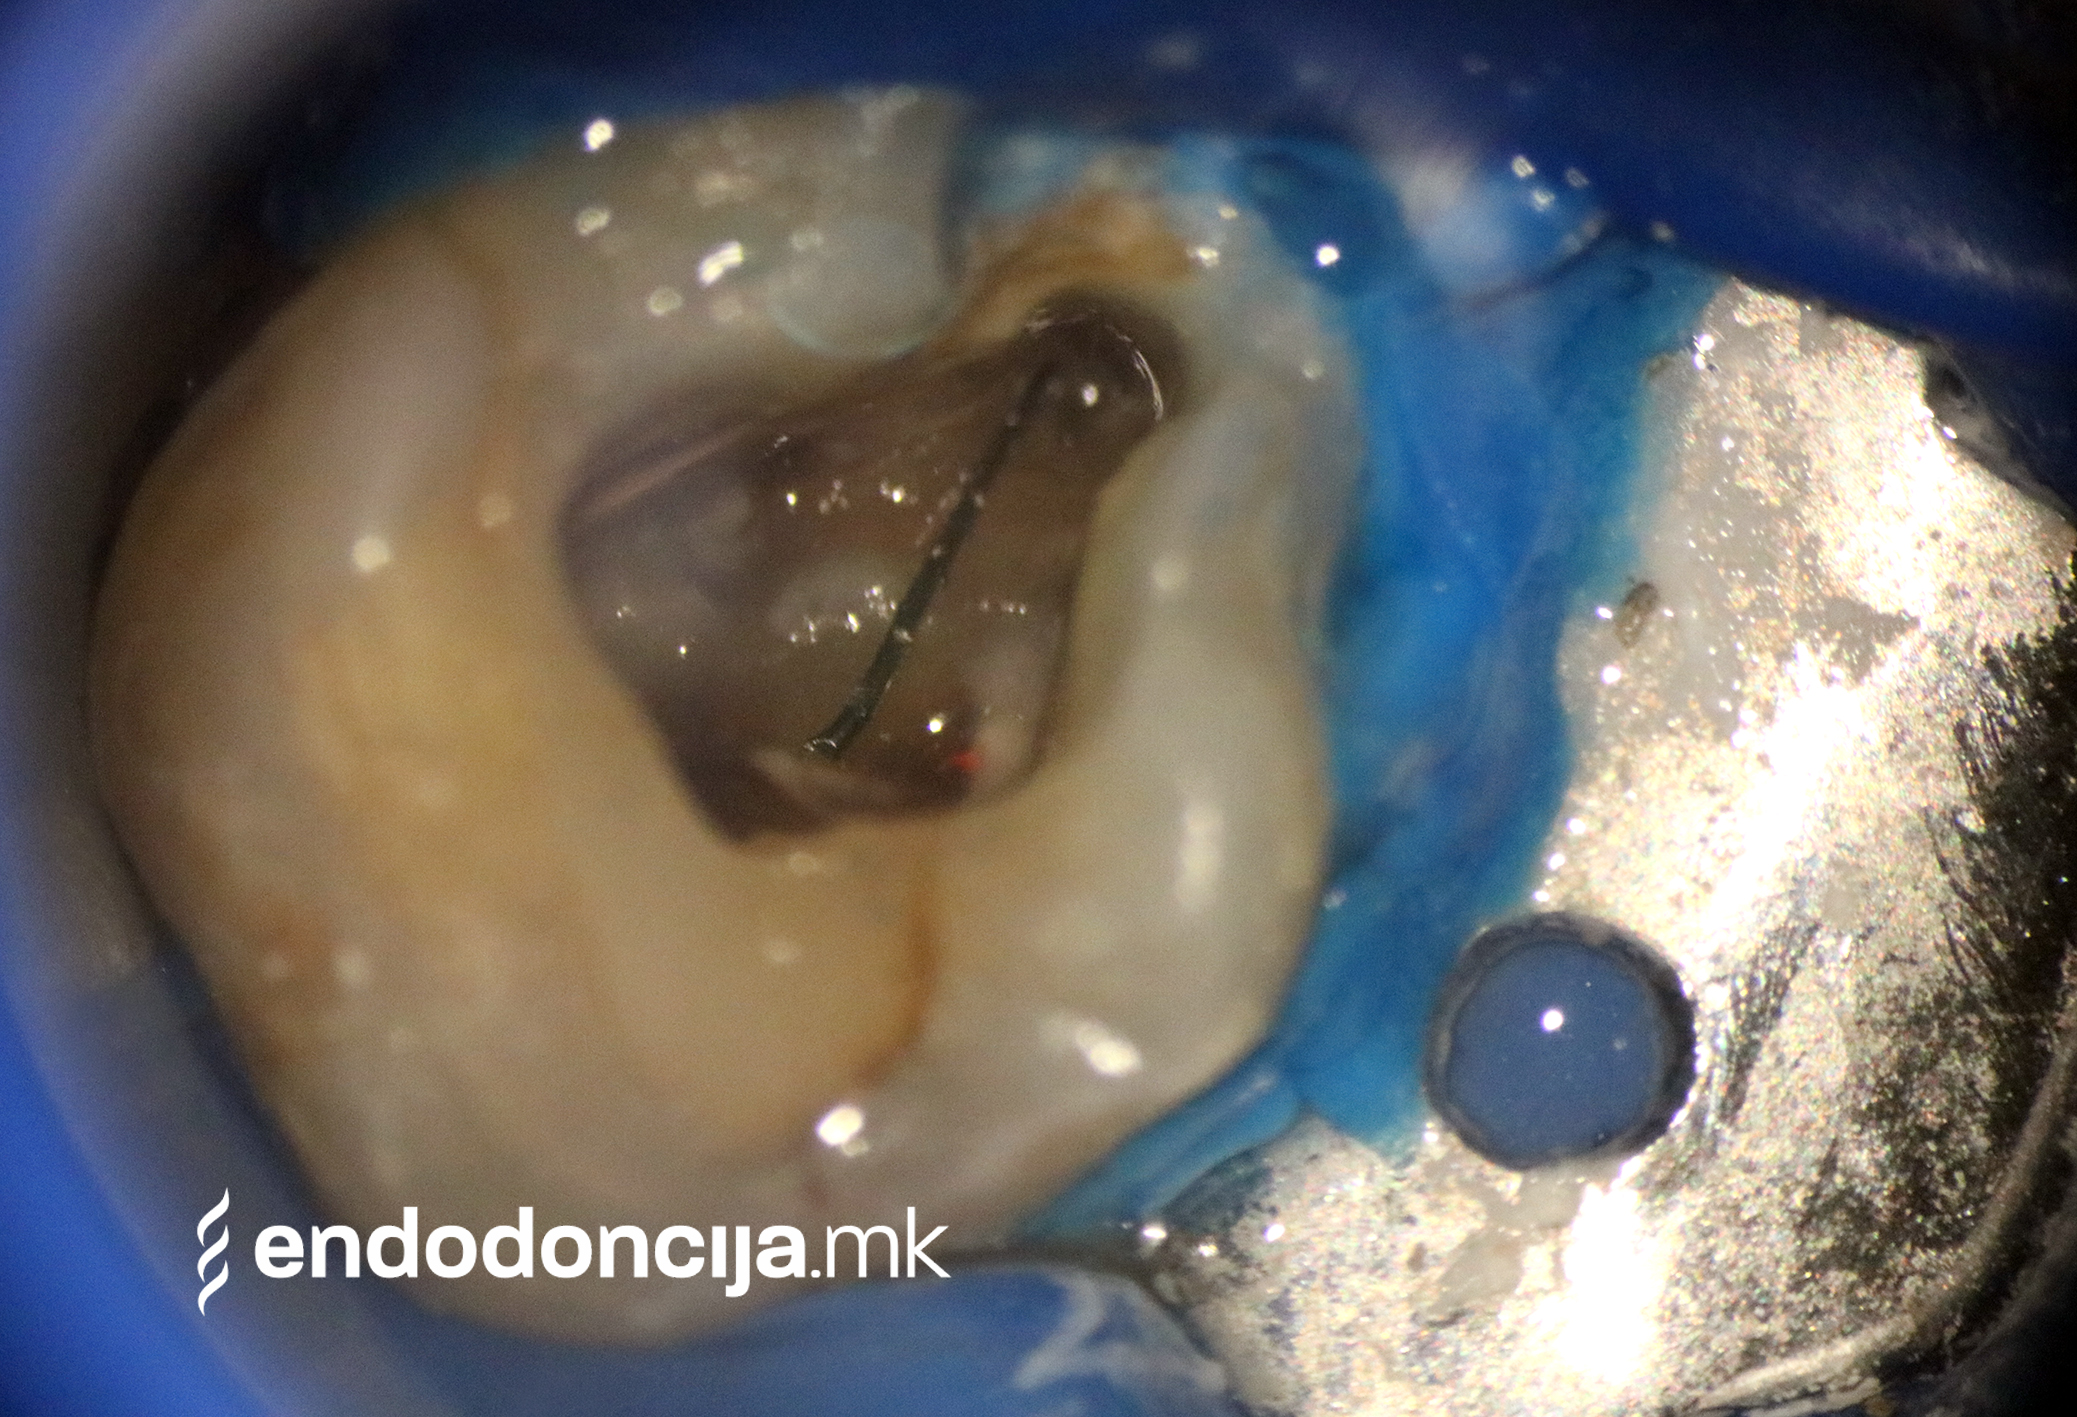

На специјализираниот оддел за ендодонција, нашите пациенти ги лекуваме на највисоко професионално и дијагностичко ниво. Опремени сме со најсовремени хируршки микроскопи, кои поддржуваат детален приказ и подготовка на коренот и нудат комплетно ново ниво на прецизност. Најновата ендодонтска опрема, инструментите и материјалите за полнење се во секојдневна употреба. На овој начин третманот станува пократок, дури и во комплицирани случаи, и се избегнува губење на забите.

Она што е импресивно е прецизноста на микроскопските третмани. Дури и кога каналите се потешко достапни, може да се лоцираат и исчистат така што релапсите се со помала веројатност. Спротивно на тоа, скриените канали често остануваат неоткриени во конвенционалниот третман на коренскиот канал и затоа не можат да се чистат. Бактериите можат да се размножуваат таму без пречки и да предизвикаат воспаленија. Ова често останува незабележано со години додека не се појави забоболка, а со тоа и компликации.

Употребата на микроскоп исто така овозможува детектирање пукнатини или фрактури што може да предизвикаат болка или воспаление.